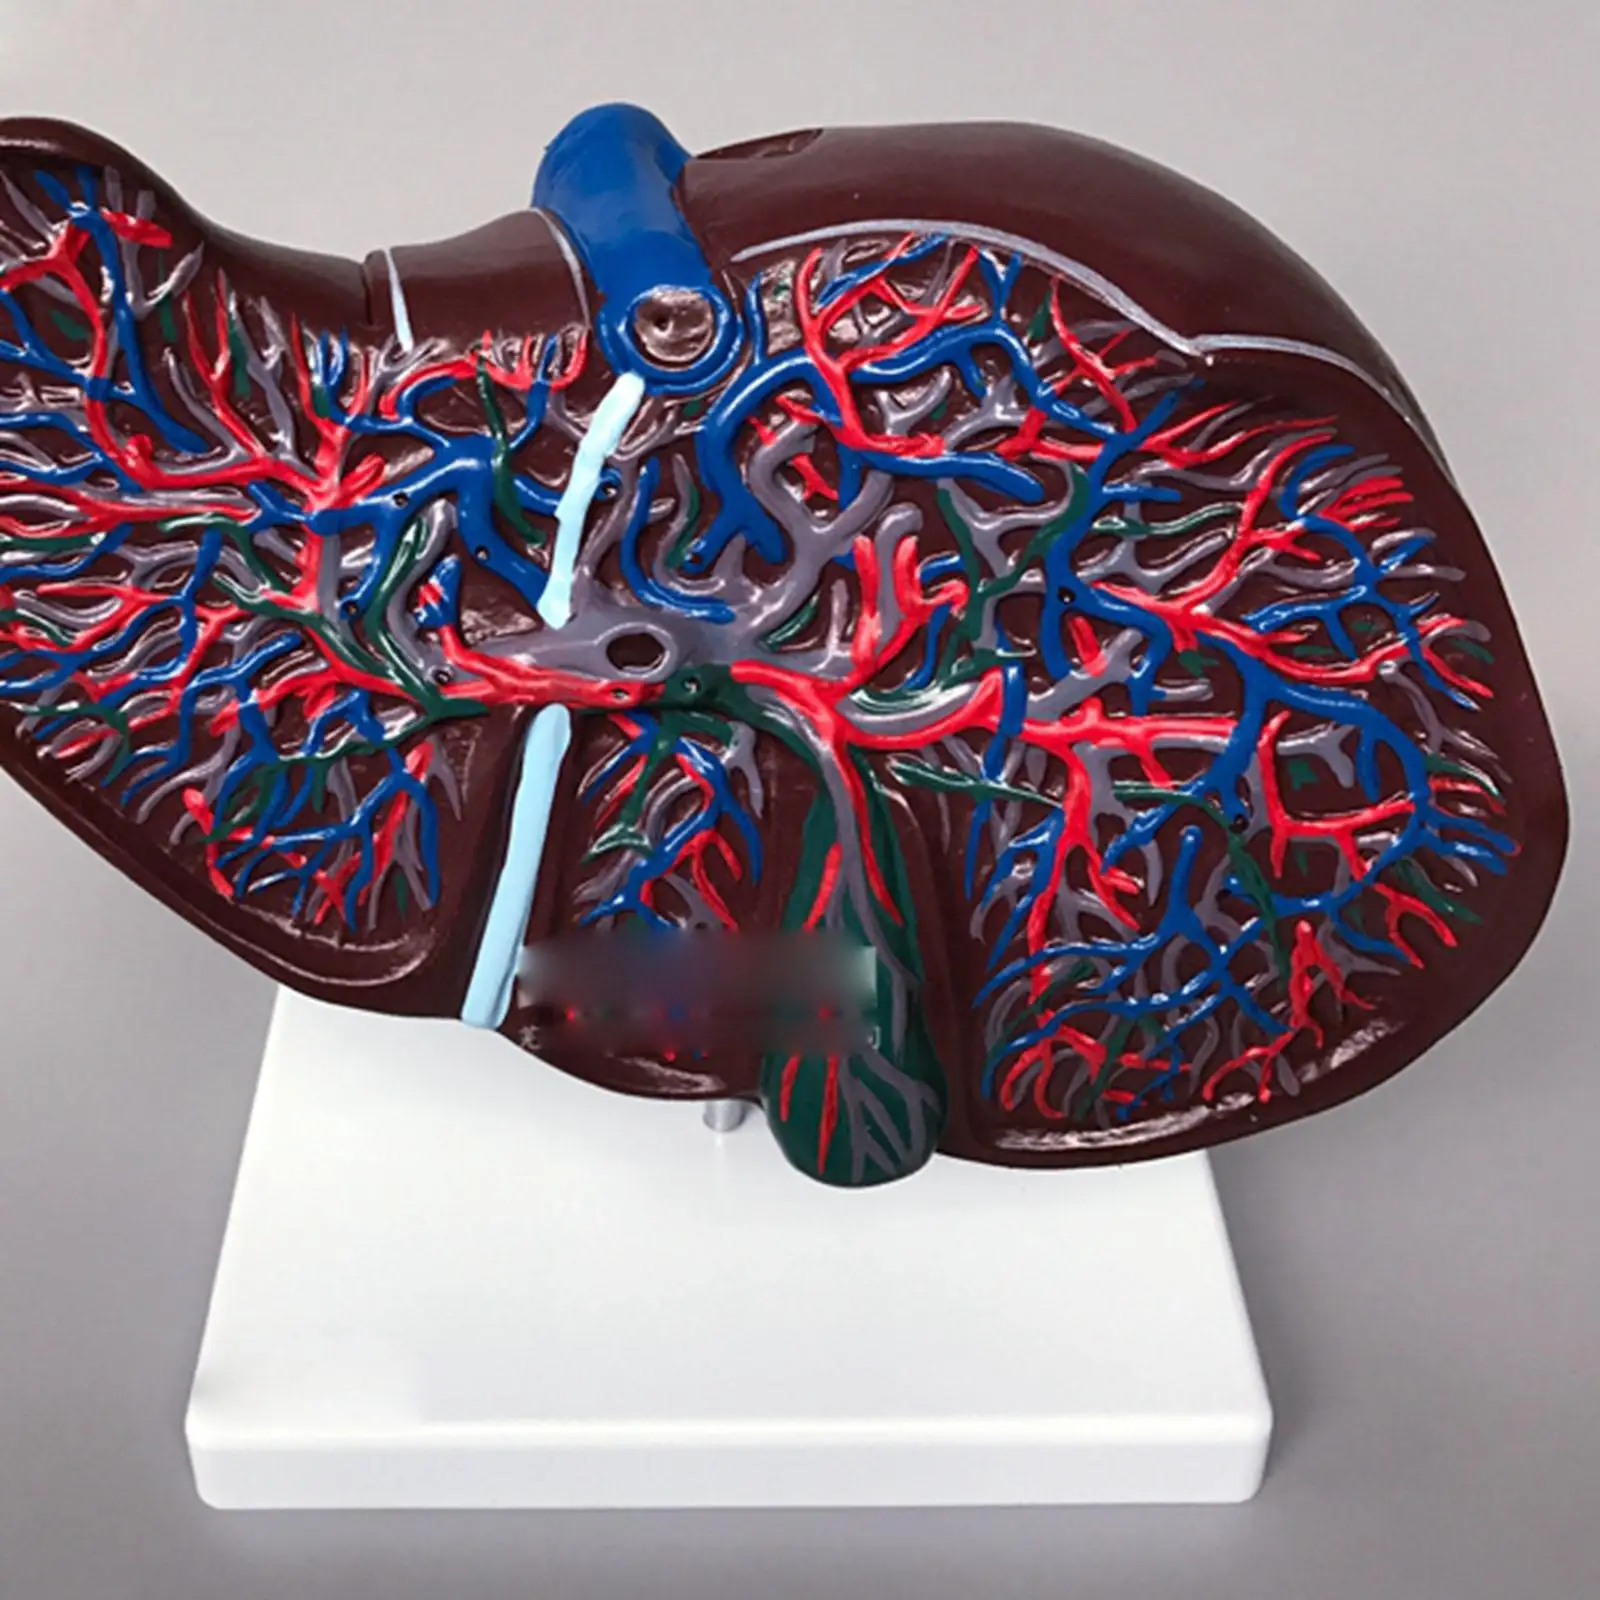

В последние годы в социальных сетях и блогах все чаще встречается необычное явление, известное как “Печень фото”. Этот термин относится к художественному стилю, при котором фотографии печени человека становятся объектом эстетического восприятия и даже искусства. Такие изображения, часто с высоким разрешением и детальной проработкой текстур, привлекают внимание не только медиков и исследователей, но и широкой публики, вызывая удивление и восхищение своей красотой и уникальностью.

Печень фото